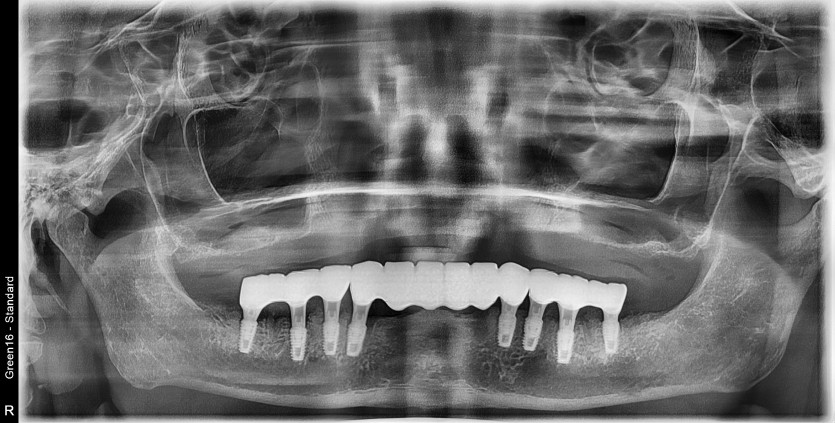

만 68세 하악 전체 임플란트 증례(상악 기존틀니 사용)

하악 전체 임플란트 증례입니다.

(상악 기존틀니 사용)

8개의 임플란트로 완성하였습니다.